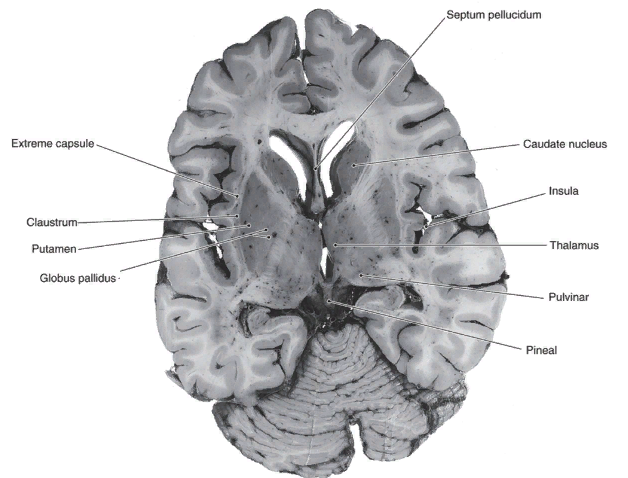

Таламический мозг включает в себя таламус, thalamus, надталамическую область – эпиталамус, epithalamus, и заталамическую область – метаталамус, metathalamus.

Таламус (зрительный бугор) это скопление серого вещества, имеет яйцевидную форму, передний конец заострен, имеется небольшой выступ – передний бугорок, tuberculum anterior, сзади таламус утолщен и называется подушкой, pulvinar. Латерально от таламуса находится хвостатое ядро, nucl caudatus. Медиальная поверхность таламуса обращена в полость III желудочка.

Эпиталамус состоит из треугольника поводка, trigonum habenularum, поводка, habenula, между поводками имеется спайка, соединяющая поводки, comissura habenularum, к ней прикрепляется шишковидное тело, corpus pineale (эпифиз).

Метаталамус включает медиальное и латеральное коленчатые тела, corpus geniculatum medialis et lateralis, которые располагаются позади зрительного бугра.

Медиальное коленчатое тело вместе с нижними холмиками среднего мозга являются подкорковыми центрами слуха, а латеральное с верхними холмиками – подкорковые центры зрения.